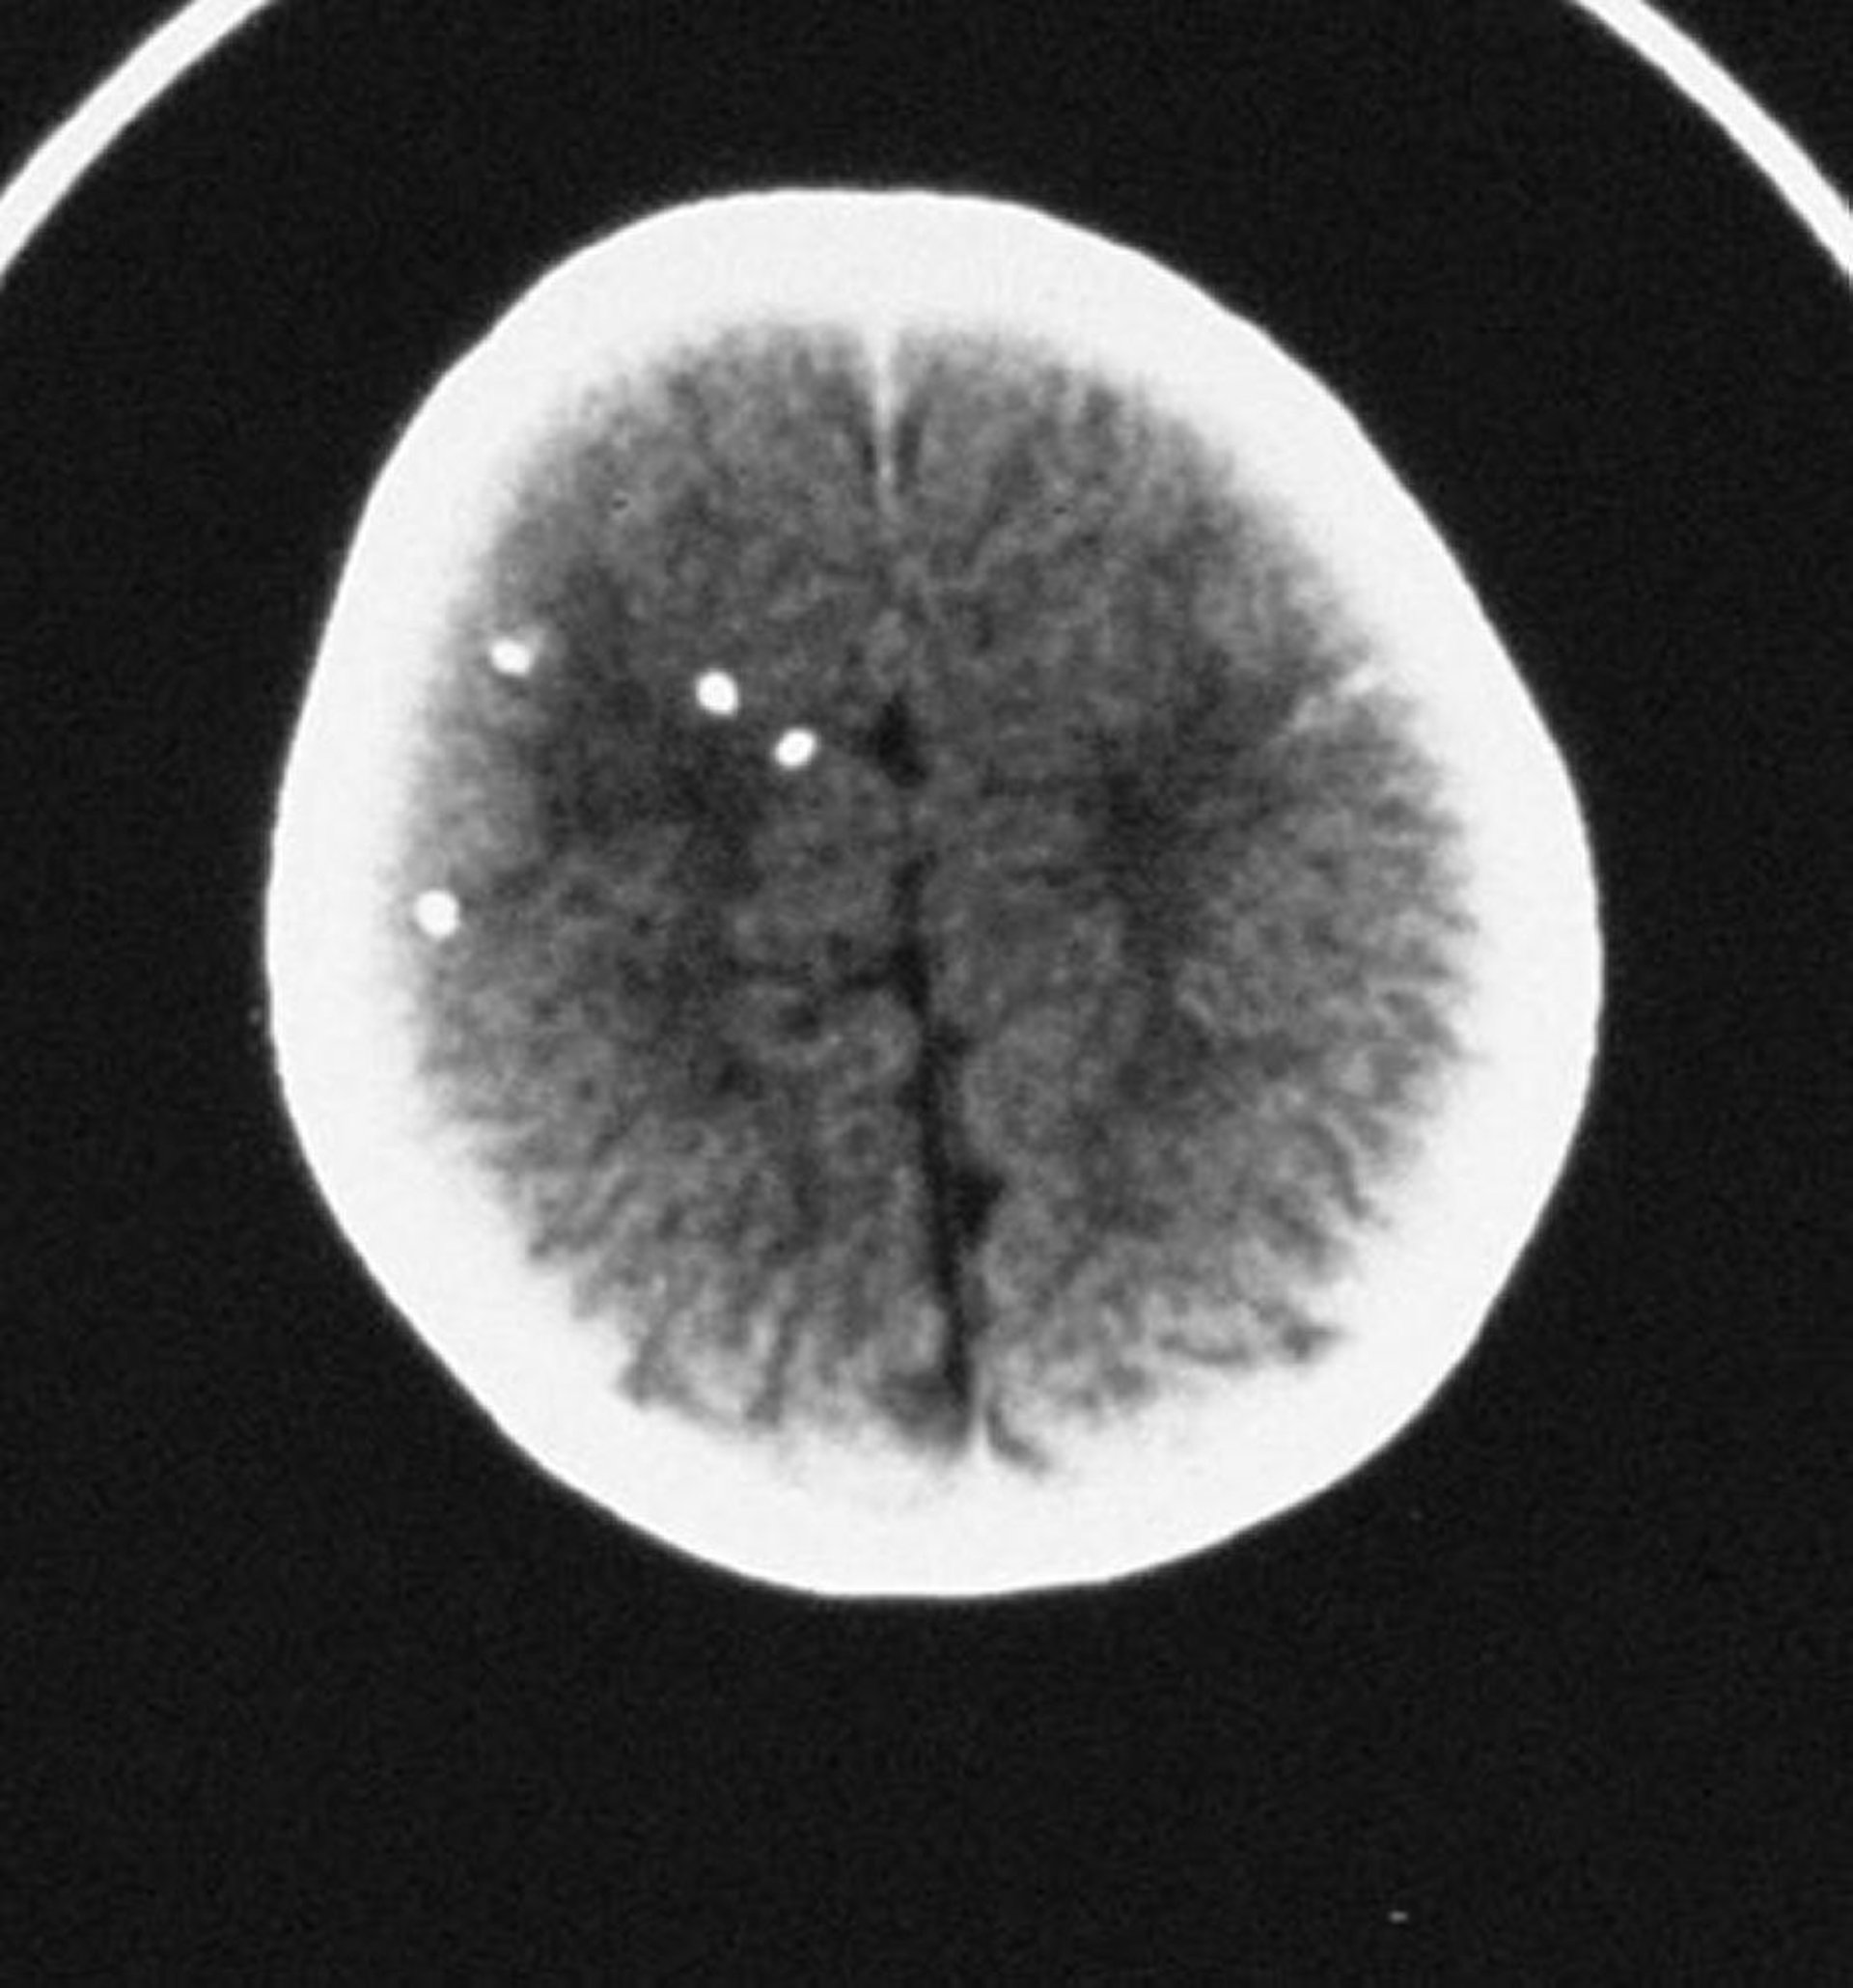

先天性トキソプラズマ症

CT上で散在性の頭蓋内石灰化を認める。